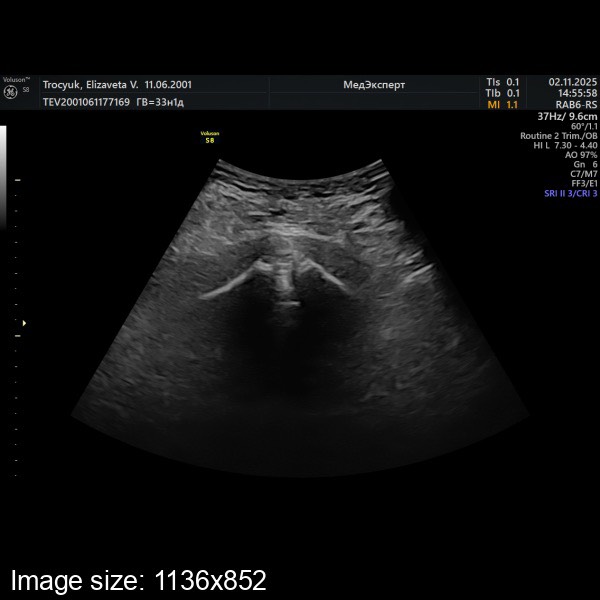

Как же я вас понимаю.. абсолютно аналогично.. началось на 33 неделе.. по узи расхождение всего 2,7 мм, а такое ощущение, будто там все 20мм.. мне еще сказали, что это может так сильно болеть из-за тазового предлежания малыша, ибо нагрузка неравномерно на таз распределена.. я жду, когда моя перевернется и должно стать легче 😩🙏🏻